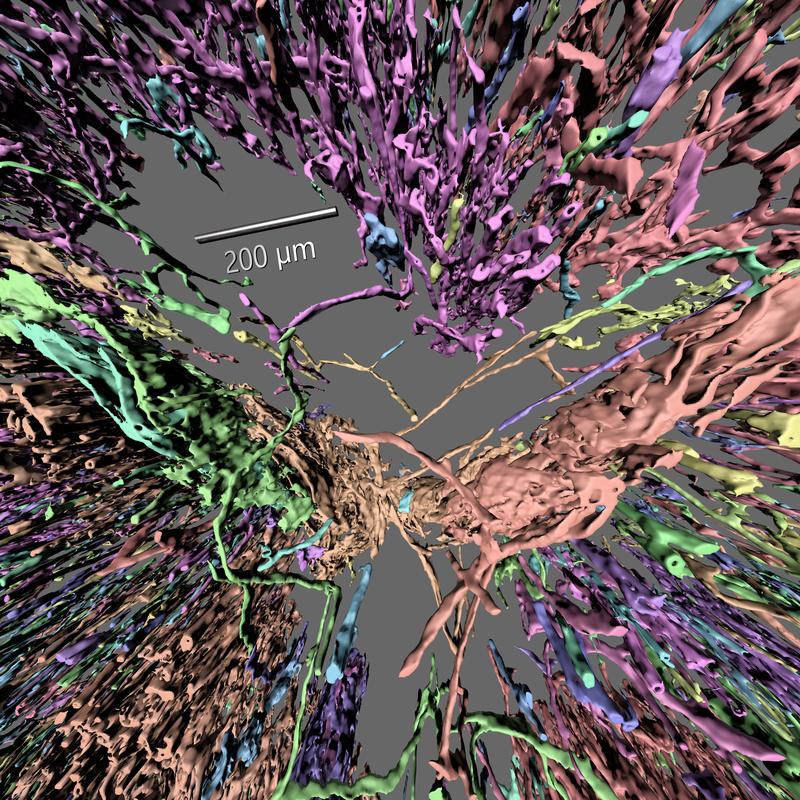

Im Netzwerk winziger Blutgefäße: Virtuelle Erkundungsreisen mit neuer Software aus Bayreuth

Die Forschergruppen um Prof. Dr. Michael Guthe und Dr. Oleg Lobachev in Bayreuth (Informatik) und Prof. Dr. Birte Steiniger in Marburg (Anatomie) haben 2017…